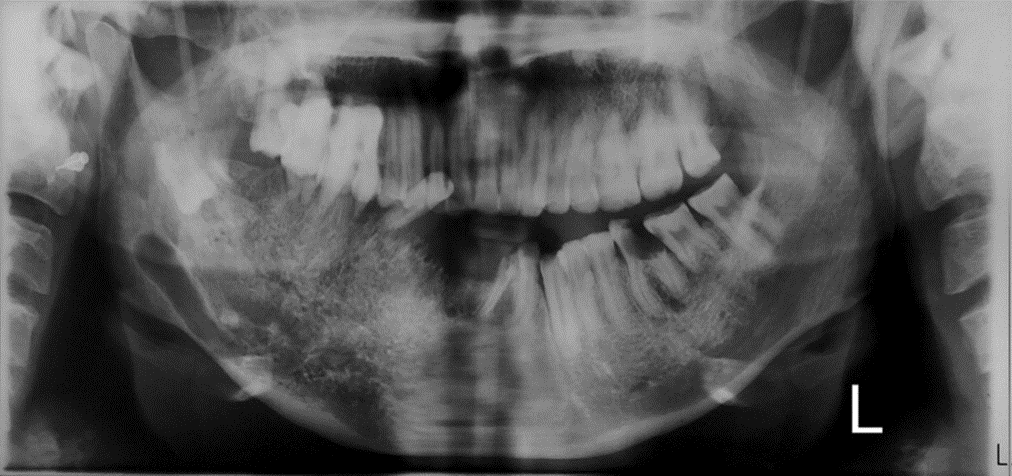

Radiográficamente, las malformaciones vasculares de las mandíbulas se han denominado «grandes imitadoras radiológicas» y pueden parecerse a cualquier lesión, desde un quiste hasta una neoplasia maligna. En la mandíbula, la malformación vascular produce una imagen radiotransparente mal definida, a menudo con apariencia de panal de abejas o burbujas de jabón, con pequeñas lagunas redondeadas y desiguales o un área perforada. Las MAV aparecen con mayor frecuencia como radiotransparencias multiloculares en exámenes panorámicos con canal alveolar inferior dilatado y ensanchamiento de los espacios medulares. Por lo tanto, se debe considerar un gran número de tumores, tanto benignos como malignos, en el diagnóstico diferencial. De las lesiones benignas, los quistes escamosos son los más frecuentes. Las lesiones menos comunes incluyen los quistes no epiteliales (también conocidos como quistes óseos hemorrágicos o traumáticos), la displasia fibrosa, el fibroma, el mixoma, el neurofibroma, el granuloma eosinofílico y los quistes óseos aneurismáticos. Dado que suele aparecer como una radiotransparencia multilocular, se considera que otras técnicas radiográficas, como la TC, la RM y la angiografía por sustracción digital (ASD), permiten obtener un diagnóstico preciso de la MAV.